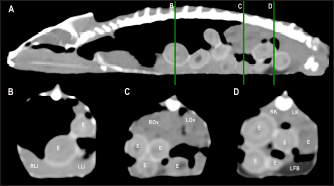

Fig. 4. Sagittal precontrast CT image displayed in soft tissue window (A) and transverse cross-sectional views of gross anatomical sections at the level of the liver (B), gallbladder (C), fat bodies (D), and kidneys (E) in a veiled chameleon (C. calyptratus). The right of the patient is on the left of the image. H, heart; RLu, right lung; LLu, left lung; Es, Esophagus; RLi, right liver lobe; LLi, left liver lobe; ST, stomach; GB, gallbladder; RK, right kidney; LK, left kidney; RT, right testicle; LT, left testicle; RFB, right fat body; LFB, left fat body; Co, colon.

Heart, liver, including caudal vena cava (CVC), hepatic vessels, and gallbladder, esophagus, stomach, intestines, cloaca, gonads, fat bodies, kidneys, and when distended, urinary bladder were identified in the CT images with the aid of the anatomical sections (Fig. 4). The spleen, pancreas, and adrenal glands could not be identified. Measurement values of the liver, testes, fat bodies, and kidneys observed in CT in veiled and panther chameleons are seen in Table 1.

Fig. 5. Sagittal precontrast CT image displayed in soft tissue window (A) and selected corresponding transverse images represented as green line section, displayed in soft tissue (B, D–G) and lung window (C) at the level of the lungs, liver (D), gastrointestinal tract (E), fat bodies (F), and kidneys/urinary bladder (G) in a panther chameleon (F. pardalis). The right of the patient is on the left of the image. RLu, right lung; LLu, left lung; Es, esophagus; RLi, right liver lobe; LLi, left liver lobe; St, stomach; I, intestine; GB, gallbladder; RK, right kidney; LK, left kidney; RT, right testicle; LT, left testicle; Co, colon; RFB, right fat body; LFB, left fat body; U, urinary bladder with intraluminal content (urate salts) in the lumen visualized as multiple irregular mineral attenuating structures.

Fig. 6. Sagittal right paramedian precontrast CT image displayed in soft tissue window (A) and selected corresponding transverse images represented as green line section, displayed in soft tissue window at the level of the gallbladder (B), fat bodies (C), and kidneys/urinary bladder (D) in a veiled chameleon (C. calyptratus). H, heart; RLu, right lung; LLu, left lung; Es, esophagus; RLi, right liver lobe; LLi, left liver lobe; GB, gallbladder; RK, right kidney; LK, left kidney; RT, right testicle; LT, left testicle; I, intestine; RFB, right fat body; LFB, left fat body; U, urinary bladder; LF, left femur; RF, right femur; PB, pelvic bone.